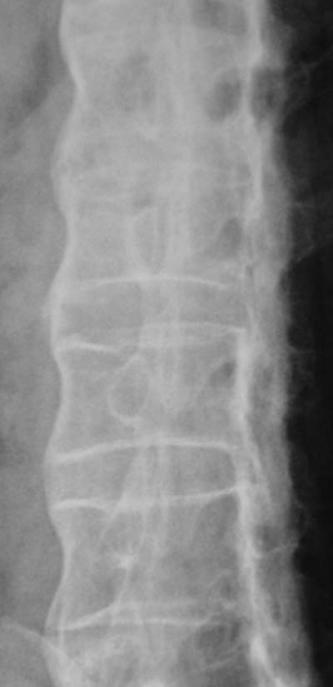

X线表现:1.骶髂关节鼠咬状骨质破坏,狭窄或骨性强直,双侧对称;2.竹节状脊柱,纤维环和韧带的骨化、椎体方形变

3.强直性脊柱炎 ( AS):以中轴关节慢性炎症为主的全身疾病,病因不明,类风湿因子阴性。病理学:非特异性炎症。;双侧骶髂关节受累;

脊柱韧带骨化—骨性强直—竹节状脊柱